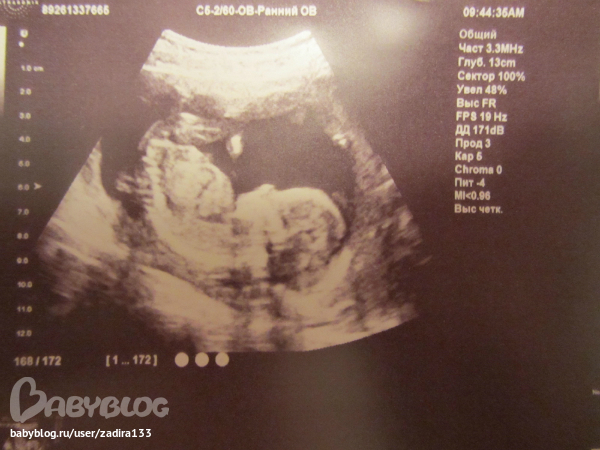

24 недели